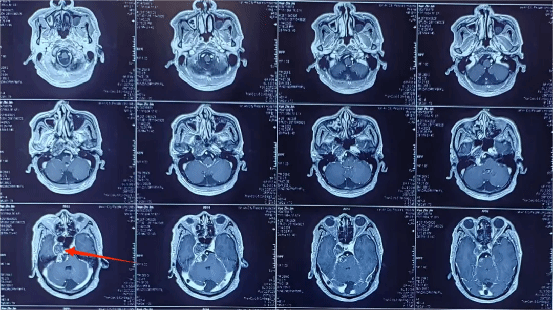

61岁薛大爷(化名),1年前出现右侧听力下降、面瘫、右眼不能外展。于外院行头颅磁共振考虑右侧桥小脑角占位,因为比邻脑干,家属考虑患者手术风险大,仅行放射治疗。一周前因突发恶心呕吐我科就诊。

入院后完善了颅脑影像检查,发现右侧桥小脑角区肿瘤已明显挤压脑干。

脑干又称“生命的禁区”,功能受损可能直接影响患者生活质量甚至危及生命安全。经神经外科学科带头人、神经外科二病区主任郭清保详细评估病情,该患者脑干已受压迫,桥小脑角区解剖关系复杂,肿瘤明显挤压脑干及右侧颈内动脉颅内段,同时因患者曾行放疗导致肿瘤与周围组织粘连,分离困难,易出血,手术难度大。